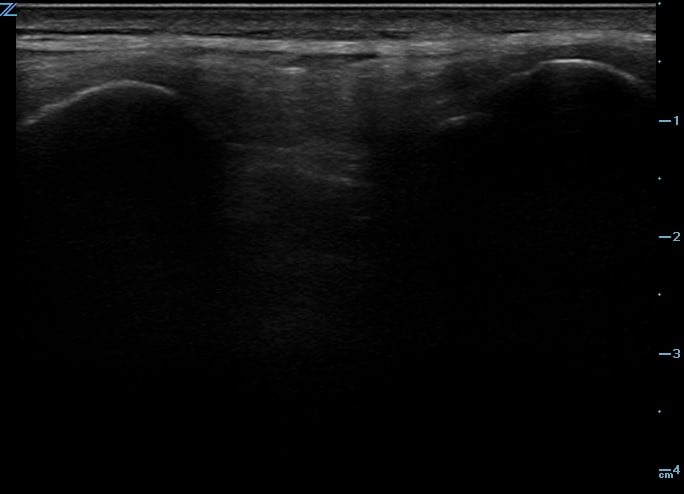

One recommended approach is to start with the probe in transverse position at the level of the sacrum and scan superiorly, sequentially identifying the spinous processes of L5, L4, L3, and L2. In the transverse orientation, spinous processes are seen as small, hyperechoic marks with dense vertical shadowing (Figure 1). With the probe centered over a spinous process, the operator uses a clean towel to wipe off excess gel, and a skin marker to place a vertical hash mark above and below the midline of the probe (Figure 2). Next, the probe is placed in longitudinal orientation over the same spinous processes, with the indicator toward the patient’s head. In this view, spinous processes will appear as wider, hyperechoic areas with distal shadowing (Figure 3). When two or more spinous processes are simultaneously visualized, the space between them is the area available for needle insertion. The skin is marked again, this time with horizontal hash marks extending outward from the midline of the probe (Figure 4).

Figure 3. Ultrasound image of spinous processes in longitudinal plane.